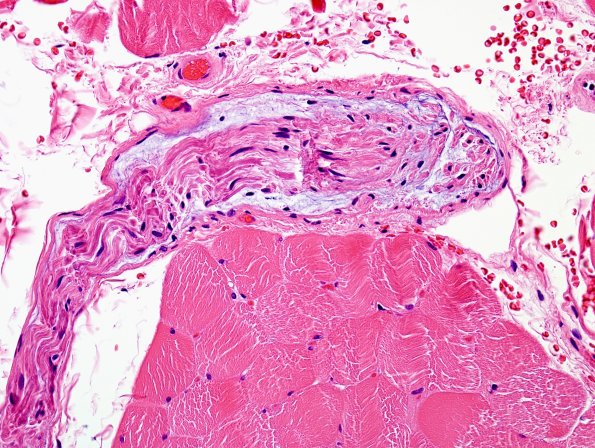

3A Edema, subperineurial (Case 3) H&E 2

The subperineurial space in this case is expanded by granular basophilic material. (H&E)